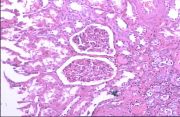

| 2021年12月10日 (五) 13:23 | 24号切片-小叶性肺炎-镜下观3.jpg (文件) |  |

154 KB | Cirno.9 | 基于MsUpload的文件上传 | 1 |